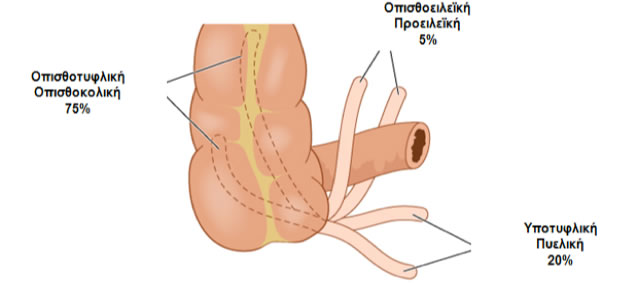

Η θέση του σώματος και της κορυφής ποικίλει και αναλόγως, η σκωληκοειδής απόφυση χαρακτηρίζεται ως: εμπροσθοειλεϊκή, πυελική, οπισθοτυφλική, υποτυφλική, δεξιά παρακολική (65% ανευρίσκονται οπισθίως και επί τα εντός του τυφλού).

Θέσεις σκωληκοειδούς απόφυσης